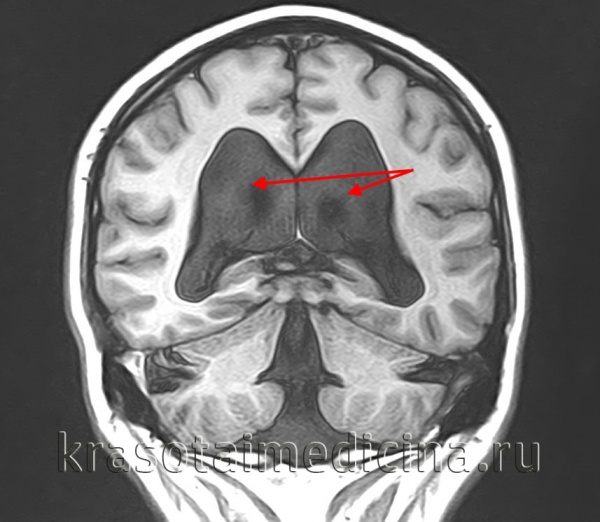

- МРТ головного мозга. Магнитно-резонансная томография в сагиттальной и аксиллярной проекции демонстрирует расширение четвертого желудочка, грубые нарушения развития мозжечка, другие структурные аномалии.